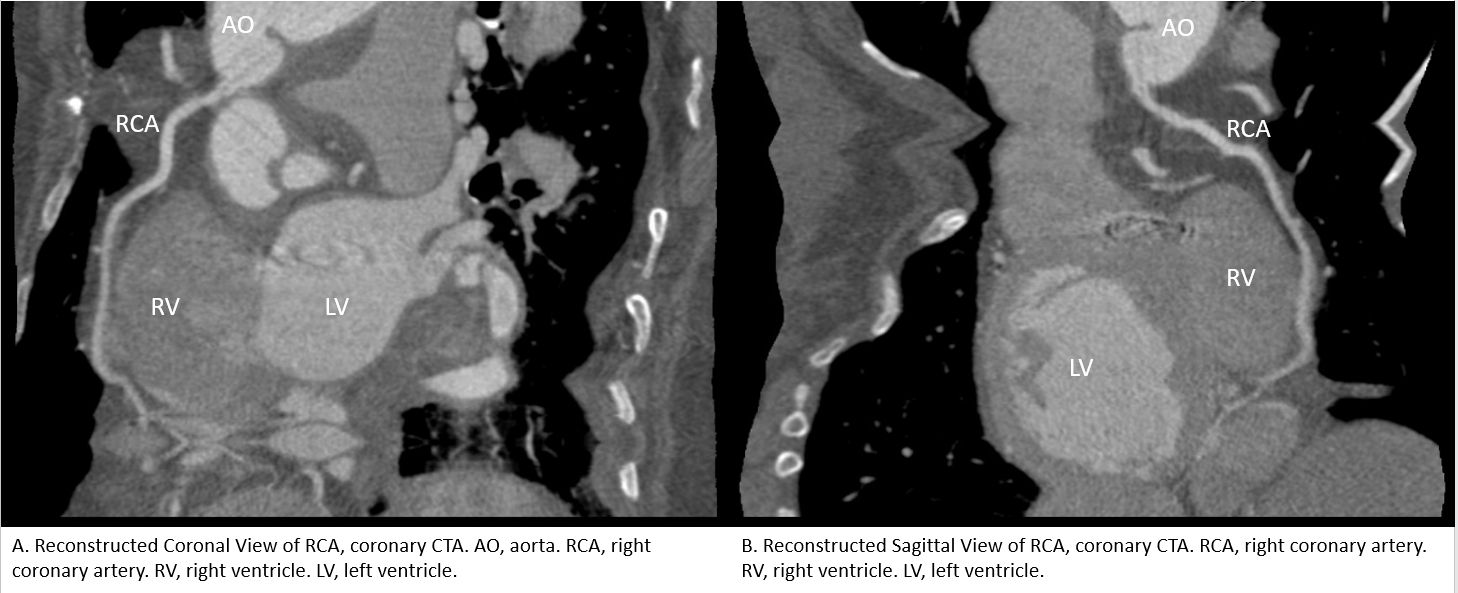

A 30-year-old female with LDS (TGFBR2 mutation) presented to the emergency room with sudden-onset chest pain radiating to her left flank. She had a complex history having initially undergone valve-sparing aortic root replacement later followed by concomitant aortic valve replacement and aortic aneurysm repair for recurrent root dilation and aortic insufficiency. She also had various dissections and aneurysms involving the aorta and peripheral vessels that were being closely monitored. Her blood pressure was 200/100. A CTA of the chest was obtained revealing a new dissection of descending thoracic aorta. High-sensitivity troponin levels rose from 33 to 1200 over 1.5 hours and EKG showed subtle, upsloping, inferior ST elevations. Emergent echocardiogram demonstrated basal to mid inferior wall hypokinesis. Blood pressure control with esmolol and clevidipine improved her chest pain. There was resolution of her ST changes on subsequent EKGs. Therefore, emergent coronary angiography was not pursued. Still, the acute myocardial injury pattern along with EKG and echocardiographic findings were concerning for myocardial infarction, particularly SCAD. Obstructive coronary artery disease was felt to be unlikely given her age and clinical context. Cardiac catheterization was discussed but deferred due to her complex vascular anatomy with dissections and tortuosity placing her at a high risk of access complications. We instead decided to obtain a coronary CTA for risk stratification. It raised concern for dissection of the RCA. However, the study was limited due to possible streaking artifact. Due to the patient’s clinical stability, a conservative approach was chosen. She was already on anticoagulation with coumadin for her history of mechanical MVR, and beta blocker therapy. No other medications were added.

SCAD in LDS is quite rare and if diagnosed, is more associated with SMAD3 mutation. In this patient population, weighing risks and benefits of making such a diagnosis is important. Here, conservative management was felt to be the best option.